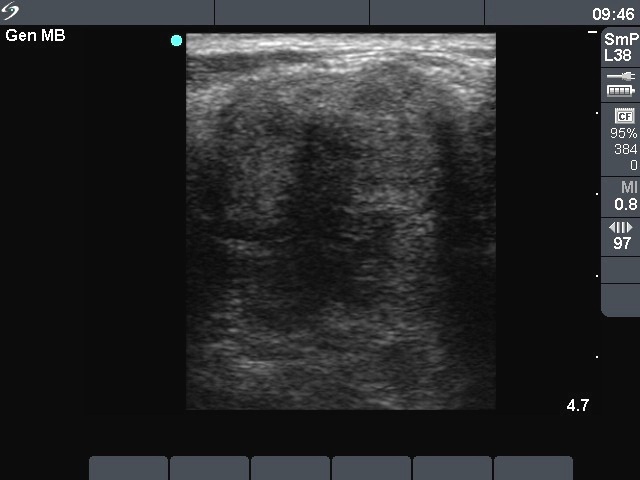

Ultrasonography. The entire left lobe was composed of multiple hypoechogenic nodules with irregular borders. They contained coarse and microcalcifications, too. A similar lesion was in the jugular area. Multiple metastatic lymph nodes were present in the left side of the neck.